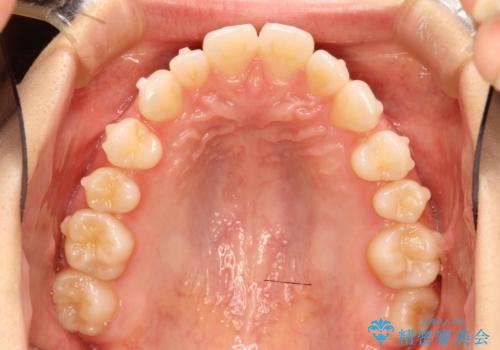

インビザラインで出っ歯を改善する 抜歯をしないinvisalign治療

- 非抜歯・遠心移動による前突の改善をマウスピースにて計画した。

非抜歯矯正の場合、大きく前歯を下げることはできませんが、奥歯の遠心移動や歯のサイズダウンにより歯軸を立て、見かけ上の出っ歯感をある程度改善することができます。